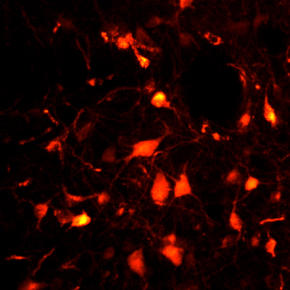

neurones

© Sara Valencia Garcia / Patrice Fort, CNRS

The glutamate neurons of the sublaterodorsal nucleus emit a spontaneous red fluorescence indicating that the viral vectors used have been successfully added.